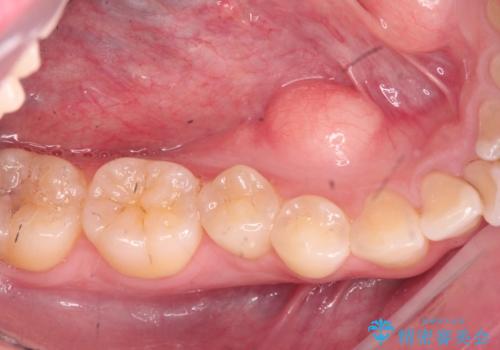

歯が割れているといわれた 奥歯にインプラントをしていきたい 全体的な治療